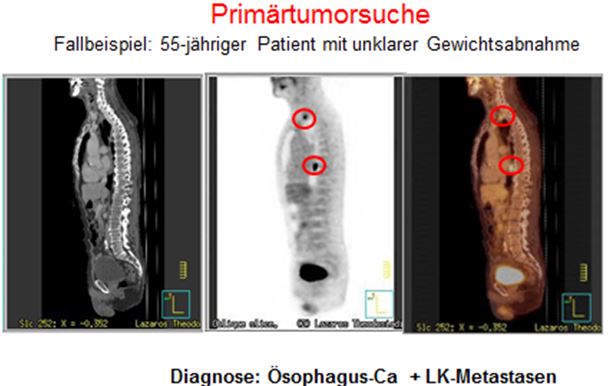

- CUP

- Oesophagus-und Magenkarzinome